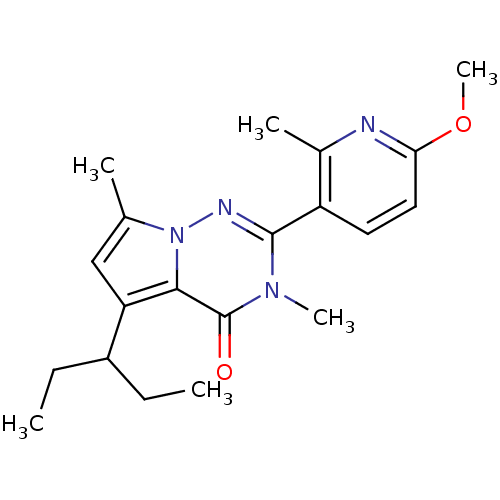

TargetCorticotropin-releasing factor receptor 1(Homo sapiens (Human))

Dupont Pharmaceuticals

Curated by ChEMBL

Dupont Pharmaceuticals

Curated by ChEMBL

Affinity DataEC50: 0.700nMAssay Description:Antagonist activity at human CRF1 receptor expressed in CHO-K1 cells assessed as inhibition of CRF-induced cAMP accumulation after 15 mins by cAMP en...More data for this Ligand-Target Pair